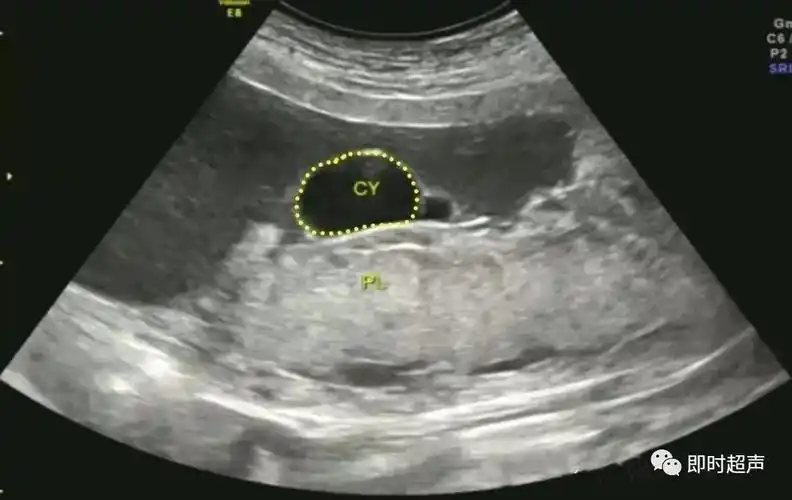

胎盘血池

胎盘血管瘤与血池

胎盘的超声评估_胎儿_前置_子宫